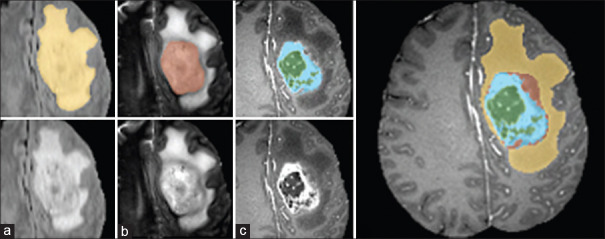

Background: Magnetic resonance (MR) image is one of the most important diagnostic tools for brain tumor detection. Segmentation of glioma tumor region in brain MR images is challenging in medical image processing problems. Precise and reliable segmentation algorithms can be significantly helpful in the diagnosis and treatment planning.

Methods: In this article, a novel brain tumor segmentation method is introduced as a postsegmentation module, which uses the primary segmentation method's output as input and makes the segmentation performance values better. This approach is a combination of fuzzy logic and cellular automata (CA).

Results: The BraTS online dataset has been used for implementing the proposed method. In the first step, the intensity of each pixel is fed to a fuzzy system to label each pixel, and at the second step, the label of each pixel is fed to a fuzzy CA to make the performance of segmentation better. This step repeated while the performance saturated. The accuracy of the first step was 85.8%, but the accuracy of segmentation after using fuzzy CA was obtained to 99.8%.

Conclusion: The practical results have shown that our proposed method could improve the brain tumor segmentation in MR images significantly in comparison with other approaches.